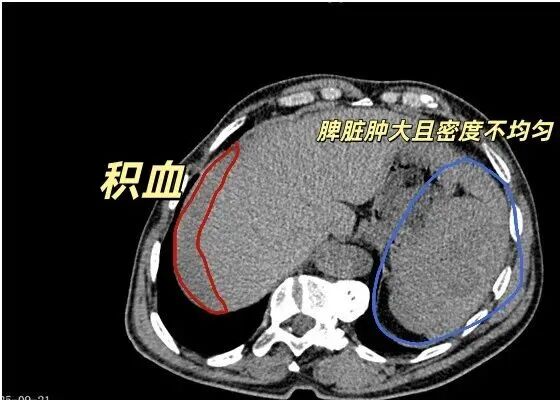

张大叔到院后,急诊绿色通道迅速启动。CT检查提示:脾脏破裂可能、腹腔及盆腔积血,脊柱侧弯,右侧肋骨骨皮质扭曲。报告为手术方案提供了关键依据。

此时张大叔已陷入失血性休克,胃肠外科张志宇主任团队立即为其行全脾切除术。术中发现腹腔积血与脾周血凝块总计约2300ml,脾脏上极有4cm裂口并活动性出血,周围网膜部分粘连,其他脏器未见损伤。